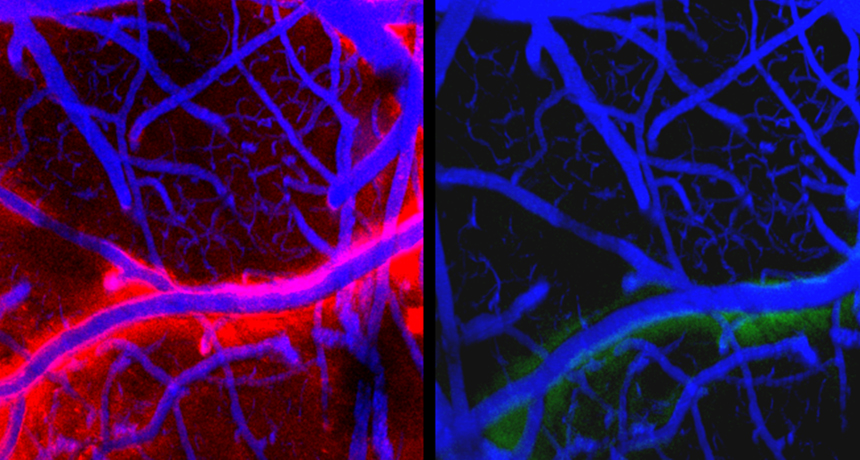

Eficienţa sistemului glimfatic este maximă în timpul somnului, fapt verificat prin experimente cu şoareci de laborator, cărora li s-a injectat, în lichidul cefalorahidian, un colorant, verde, pentru timpul somnului, şi roşu, după trezire. Aşa s-a putut observa că a existat un flux mult mai mare de lichid în timpul somnului, că spaţiile dintre celulele creierului au devenit cu 60% mai largi (celulele micşorându-se cu acelasi procent si revenind ulterior la normal), permiţând fluidului să circule mai uşor.

În urmă cu trei ani, el a decis să insiste pe harta sistemului limfatic şi a introdus în corpul unor şoareci de laborator o genă fosforescentă de meduză, ale cărei vase limfatice se luminau când erau expuse la o lumină de o anumită lungime de undă. Astfel a observat ceva care strălucea în creierul şoarecilor. Iniţial a crezut că este o greşeală în experiment, dar l-a repetat şi a observat acelaşi lucru – vasele limfatice ajungeau la creier.

Cercetătorii au identificat două sisteme de vase: unul care înconjoară creierul şi celălalt in interior. Primul este numit “sistem limfatic al creierului”, al doilea este “sistemul glimfatic”, care elimină deşeurile metabolice.